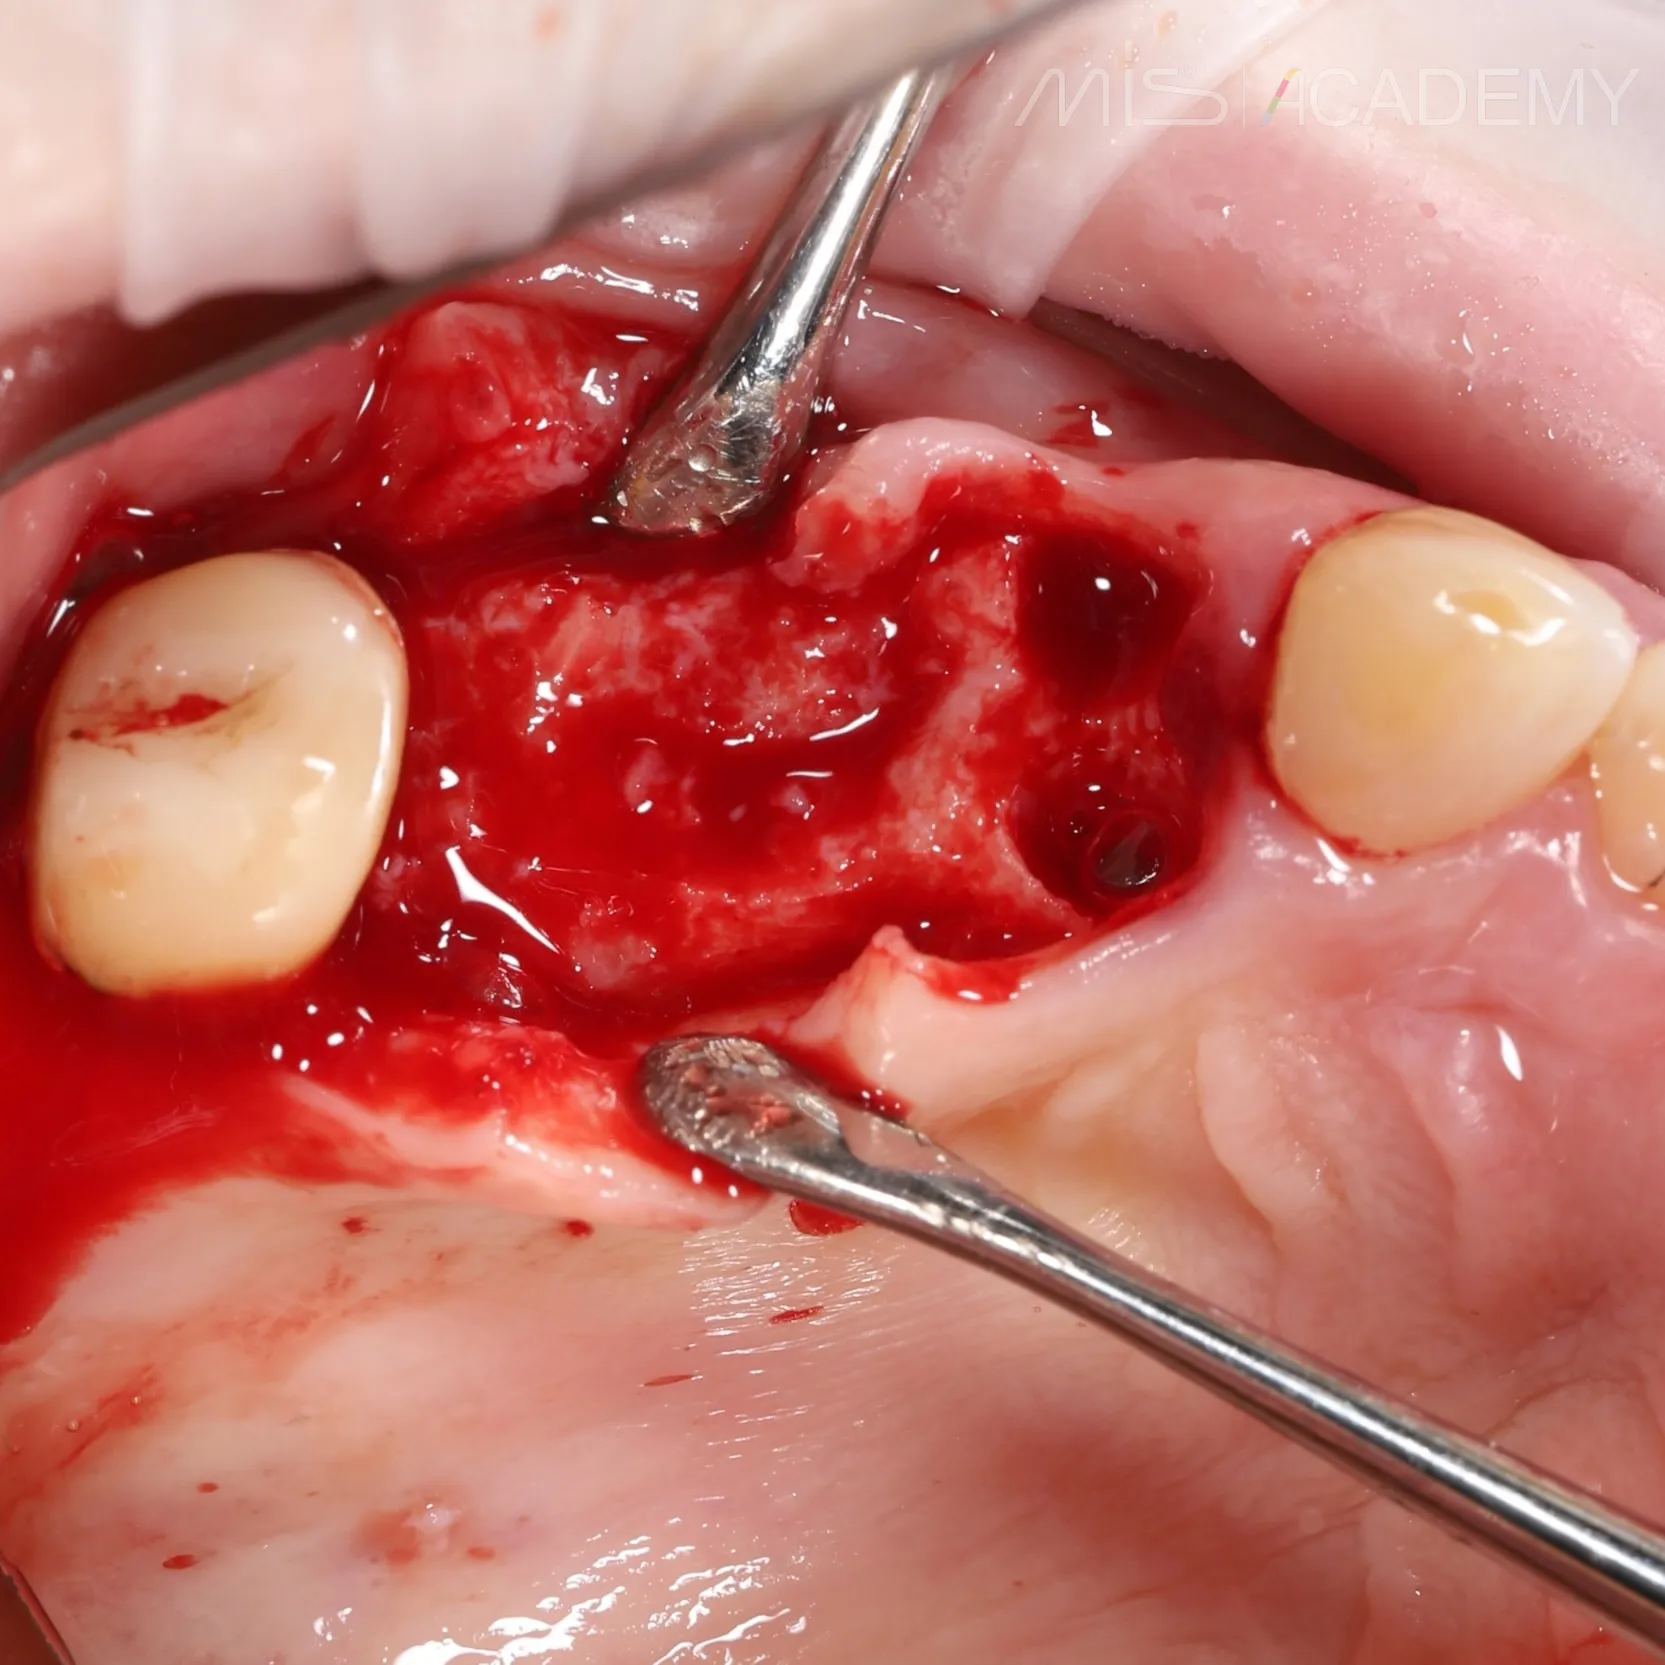

Произведено удаление зуба 2.4

— Одномоментная установка имплантата в области 2.4.

— Установка имплантата в области 2.6 с закрытым синус-лифтингом.

— Установка произведена с помощью хирургического шаблона.